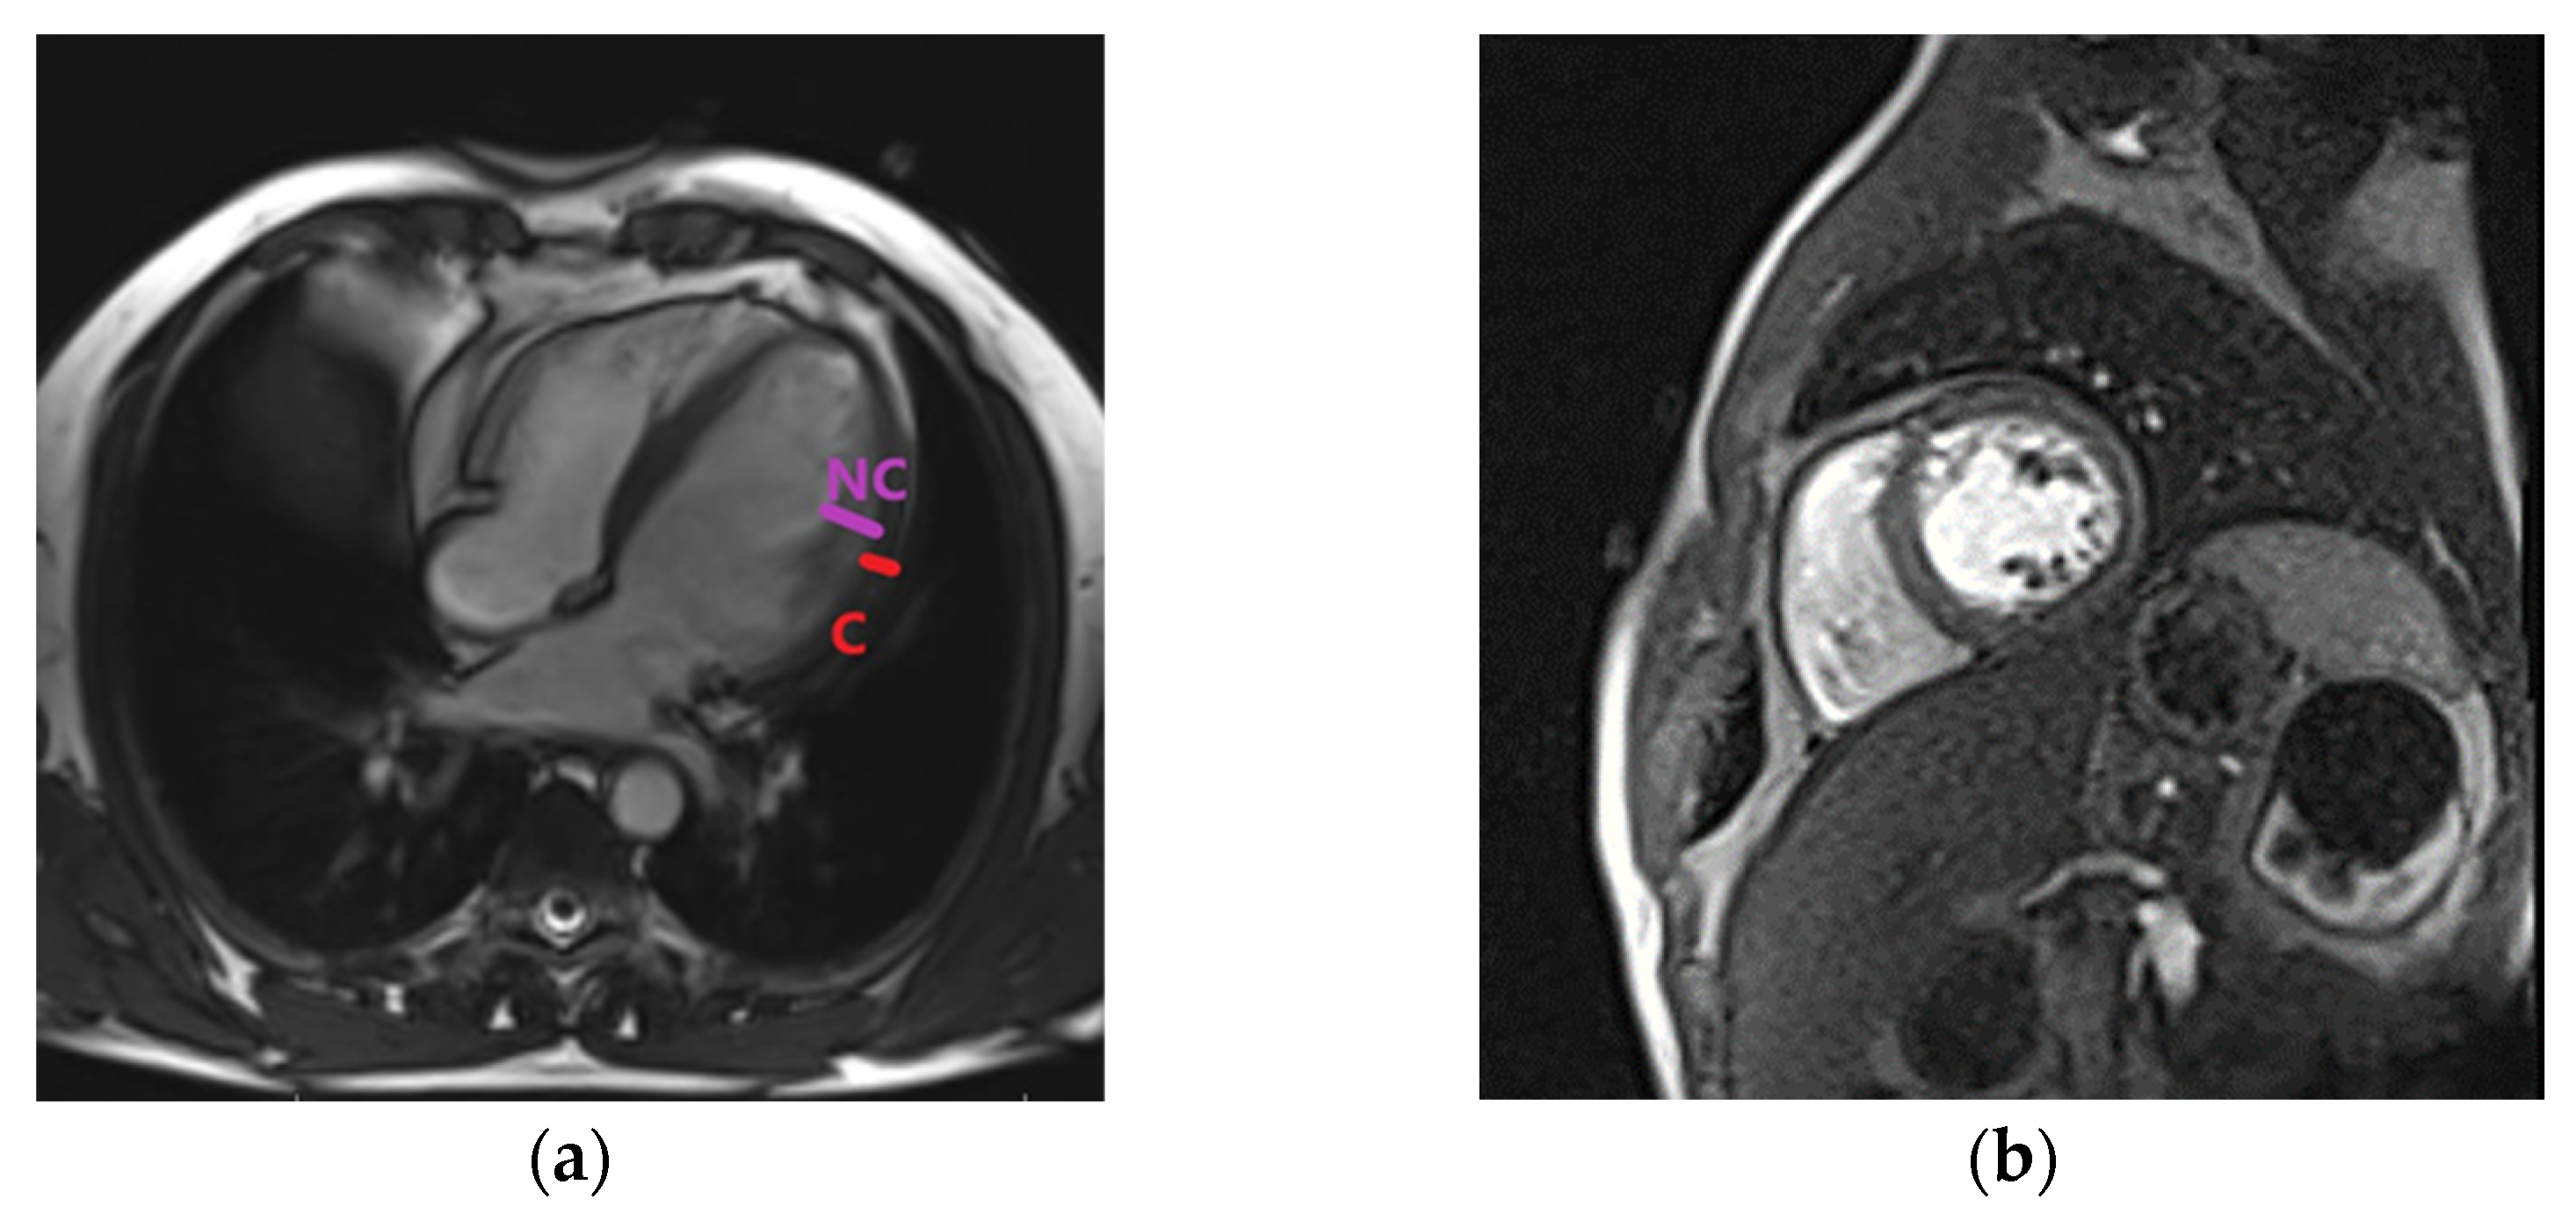

A coronarography showed normal epicardial coronary arteries and excluded the ischemic etiology of HF. Genetic tests were not available for our patient. The patient was scheduled for a CMR evaluation and a further clarification of the diagnosis. HF treatment was administered in accordance with the ESC guidelines. ACE inhibitors were replaced after a washout period of 36 h with ARNI- sacubitril/valsartan at 100 mg/day, which was titrated to 200 mg/day after 2 weeks and an increased dosage of up to 400 mg/day after another month. Loop diuretics, MRA, and betablockers were continued, and anticoagulants were also associated. SGLT-2 inhibitors were not prescribed because at that time, they were not available in our hospital and were not sustained on free prescription by the healthcare system. There was a significant clinical improvement at 6 months after discharge; the patient was in the NYHA class I, and no symptoms were present. CMR processing was performed (using Siemens Magnetom_Essenza 1.5 T., Siemens Shenzen Magnetic Resonance LTD, Shenzen, China) at this time, and it confirmed the diagnosis of LVNC by identifying trabeculations that were located at the apex and medial levels of the anterior and lateral walls of the LV. The ratio between the non-compacted and compacted layers was 2.3 during diastole at the level of the lateral wall, fulfilling the Petersen criteria for diagnosis (Figure 3, own archive of the last author).

Figure 3.

Cardiac magnetic resonance. (a) Left ventricular non-compaction in four chamber view. NC, non-compacted; C, compacted LV wall. (b) Left ventricular non-compaction in short-axis view.

The LV was dilated, but significant reverse remodeling was observed at the time of echocardiography and CMR. LV and LA volumes were diminished compared with the initial evaluation, but contractility and LVEF were significantly improved. LGE was not detected in the CMR. After one year, the patient was free of symptoms, and a further improvement was observed at the time of echocardiography regarding the ejection fraction and left heart volumes (Table 1); however, increased trabeculations persisted. Figure 4 describes an algorithm used for the diagnosis of LVNC and illustrates the evolution of several parameters after treatment initiation. The clinical, biological, and echocardiographic elements showed a significant improvement, especially after 12 months of treatment.